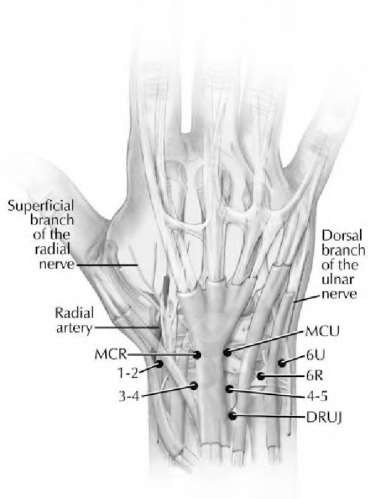

A 20-year-old park ranger trips and falls onto his right wrist with the wrist in extension and pronation. The local urgent care orders both radiographs and a CT, which you review and determine to be normal. The patient complains of ulnar-sided wrist pain. On exam, his tenderness is localized to the fovea. Ulnar deviation also causes him pain. There is no snapping sensation with wrist supination, flexion, and ulnar deviation. He otherwise has 5/5 strength to his first dorsal interosseous muscle with 4mm static two-point discrimination on the ulnar side of the 4th digit. Which of the following injuries is most likely responsible for his symptoms and exam?